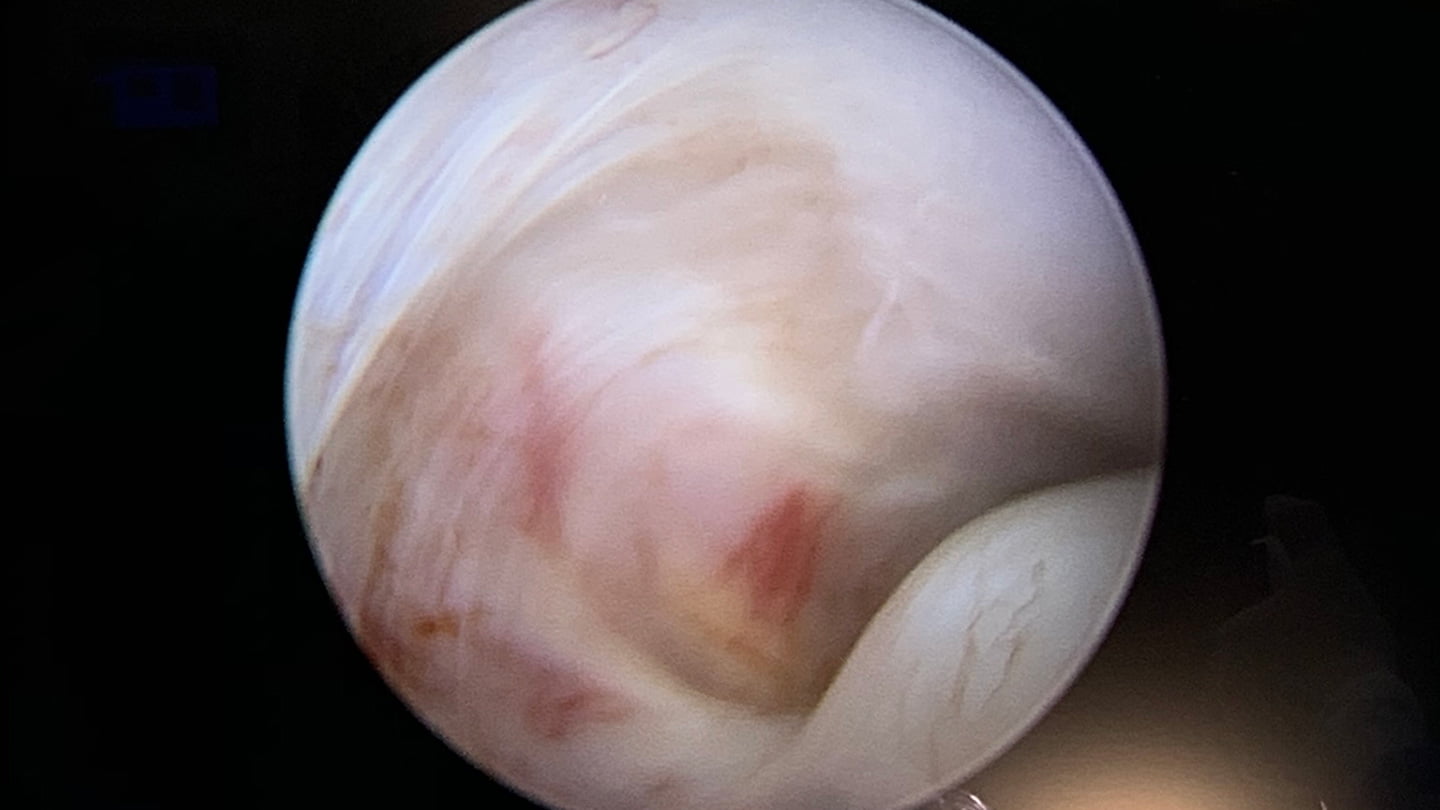

Pacientes com restrição prolongada da abertura da boca, com deformidades articulares ou com dor articular que não responda a métodos não invasivos podem ser candidatos à cirurgia. Principalmente nos transtornos que determinam dor ou limitação de movimento, as abordagens minimamente invasivas são desejáveis, por meio de procedimentos artroscópicos. As cirurgias abertas da articulação são indicadas como opção complementar, ou em casos onde a alteração da forma da articulação tenha repercussões funcionais ou mesmo na morfologia facial.